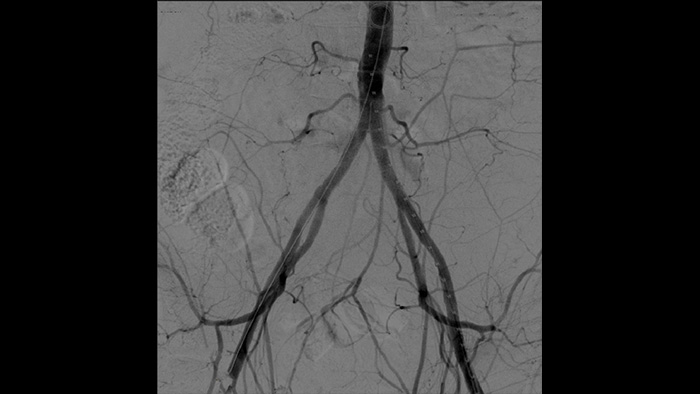

インターベンショナル血管治療で必ず必要になるDSA処理は、血管の視認性を下げる要因に繋がる構造を除去する技術を用いて血管を明確に描出させます。ロードマップでは事前に撮影した差分画像がライブ透視にオーバーレイされることで造影剤の削減に繋がります。